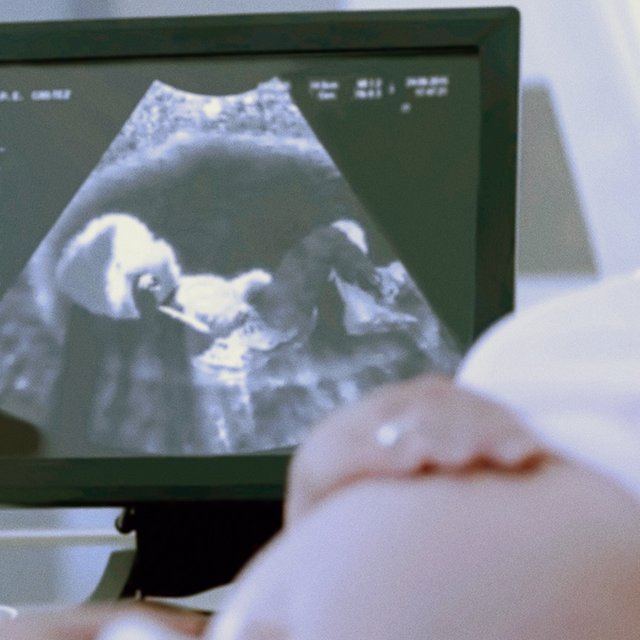

Национальная комиссия по здравоохранению Китая опубликовала рекомендации для повышения рождаемости в стране. В частности, они предложили сокращать количество абортов — раньше в КНР их в том числе делали принудительно, чтобы в семье рождалось не более 1 ребёнка.

Меры обусловлены падением уровня рождаемости в Китае. Ожидается, что в 2022 году в стране на свет появится меньше 10 миллионов детей. В 2021 году в КНР родилось 10,6 миллиона младенцев, что на 11,5% меньше, чем в 2020-м.

КНР остаётся лидером по количеству абортов. Согласно исследованию Института Гутмахера, который занимается изучением репродуктивного здоровья, абортами заканчиваются 78% незапланированных беременностей — в мире так происходит в 61% случаев. В период с 2015 по 2019 годы, по данным исследования, насчитывалось 17,7 миллионов абортов ежегодно.